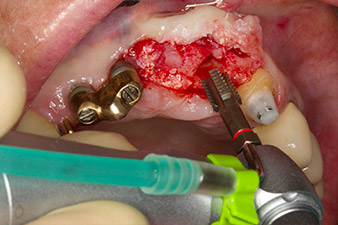

Motorized placement of the implant

Fig. 4: Motorized placement of the implant with the WS-75 L contra-angle handpiece at a ratio of 20:1 (programme P5).

In order to compensate for the periodontal bone loss and achieve an aesthetically pleasing result, the implantation was combined with guided bone regeneration (GBR) with xenogenic replacement material and a collagen membrane

(Fig. 5 and 6).